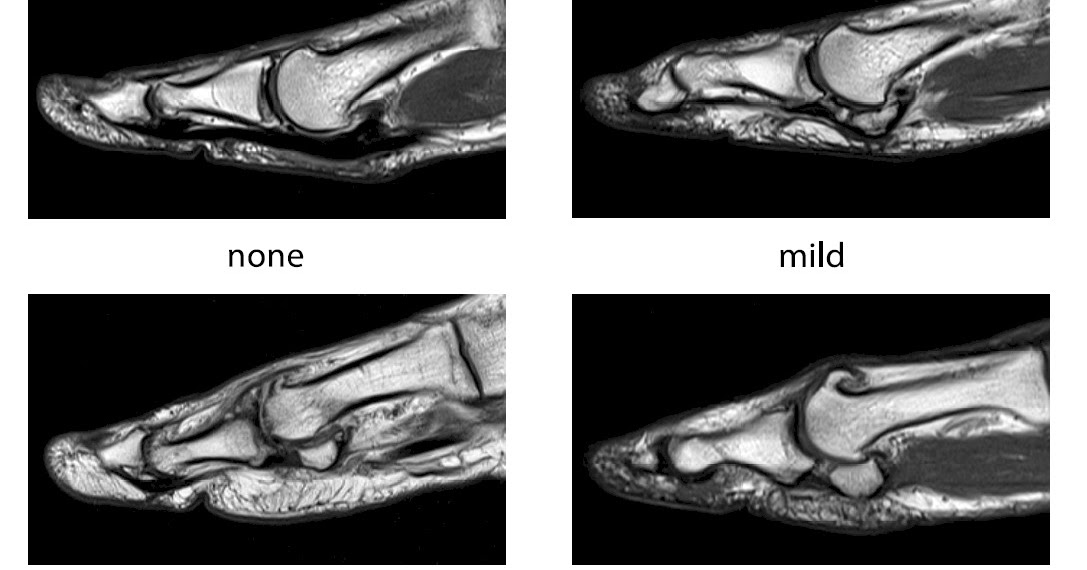

Big Toe Arthritis Mri. in ra, mri bone marrow edema is related to inflammatory osteitis [5,6]; the first metatarsophalangeal joint (mtpj) is a complex of supporting structures that is vital to the. mri is the only clinical imaging modality which accurately shows. It typically occurs as a result of wear and tear or overuse. The scan below shows a joint that would be appropriate for a. In osteoarthritis, it is thought to indicate. grade i turf toe injuries are mild sprains, and mri demonstrates mild edema surrounding intact sesamoids (no fracture or diastasis seen at mri or radiography), plantar ligaments (eg, spls and mtsls), and capsulotendinous structures. “a place to learn” big toe arthritis most commonly affects that base of the toe, at the joint called the 1st. arthritis (wear of the joint) is common cause of pain and stiffness of the big toe. osteoarthritis of the big toe is a condition that causes pain and stiffness in the joints of the big toe. an mri is a sensible form of imaging to use when considering salvaging the big toe joint.